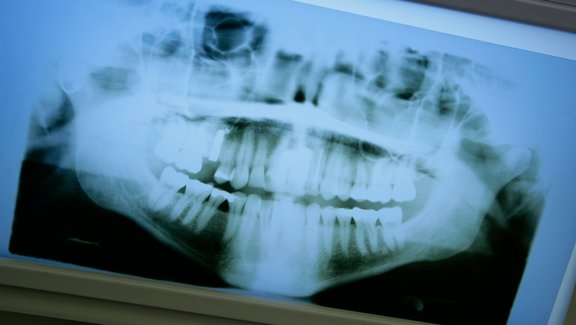

Röntgen

Die Zähne zu röntgen ist ein wichtiger Teil der Diagnose.